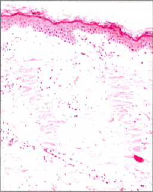

1550nmの波長(当院のレーザー)は水に吸収される波長で水に吸収後、熱に変化しますが(皮膚の70%は水です)、皮膚を削らないレーザー(non-abrative)です。

図1,2のように直径200μm以下のマイクロレーザービームを1cm2あたり50~500個、表皮から真皮深層まで照射します。

マイクロレーザービームが表皮から真皮の深部まで数多いマイクロネクロティックコラムを形成 |

正常な周辺組織に対する自然な再生促進効果で表皮とコラーゲンリモデリングが同時進行 |

すると照射部位はハリ状に熱凝固(図3)を起こします。

しかし、そのまわりは正常な組織なので創傷治癒過程つまりキズを治す力が働き、コラーゲンやエラスチンおよび表皮が再構築されるのです(図4)。

つまり人工的にキズを作って周囲の正常組織からの自然治癒力を促すことにより皮膚を再生させるのです。